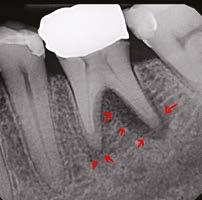

USA, Savannah, Georgia) and gutta percha via continuous wave condensation. EndoSequence BC liner blue (Brasseler USA, Savannah, Georgia) was placed over the gutta percha at the canal orifice, and the tooth was temporized using a cotton pellet and Fuji IX placed in the access (Figure 6). Following completion of the root canal, the patient was scheduled for a 3-month reevaluation and referred to her provider for definitive restoration. Healing was observed at the 3- and 6-month postoperative visits. Periapical radiographs were exposed at each visit revealing bony healing (Figure 7). The patient reported no pain or symptoms following nonsurgical root canal treatment. At both visits, percussion and palpation were negative. A CBCT was captured at the 6-month postoperative exam to evaluate healing. Coronal CBCT slices revealed a reduction in lesion size to 3.5 mm x 1.6 mm. Sagittal slices also showed reduction in lesion and maintained health of bone surrounding implant No. 12 (Figure 8). A 2011 article by Ng outlines eleven factors that, if present, improve periapical healing following primary non-surgical root canal treatment.17 Only two of these eleven factors, absence of a preoperative periapical lesion and size of the preoperative periapical lesion, were not met in this case report. Along with this and the 2017 AAE Treatment Options for the Compromised Tooth: A Decision Guide article, the final prognosis for healing is favorable.16

Figures 8A-8B: CBCT was taken at the 6-month postoperative visit. 8A. Coronal CBCT slices revealed a reduction in lesion size to 3.5 mm x 1.6 mm. 8B. Sagittal CBCT slices revealed a reduction in lesion size and maintained health of bone surrounding implant No. 12